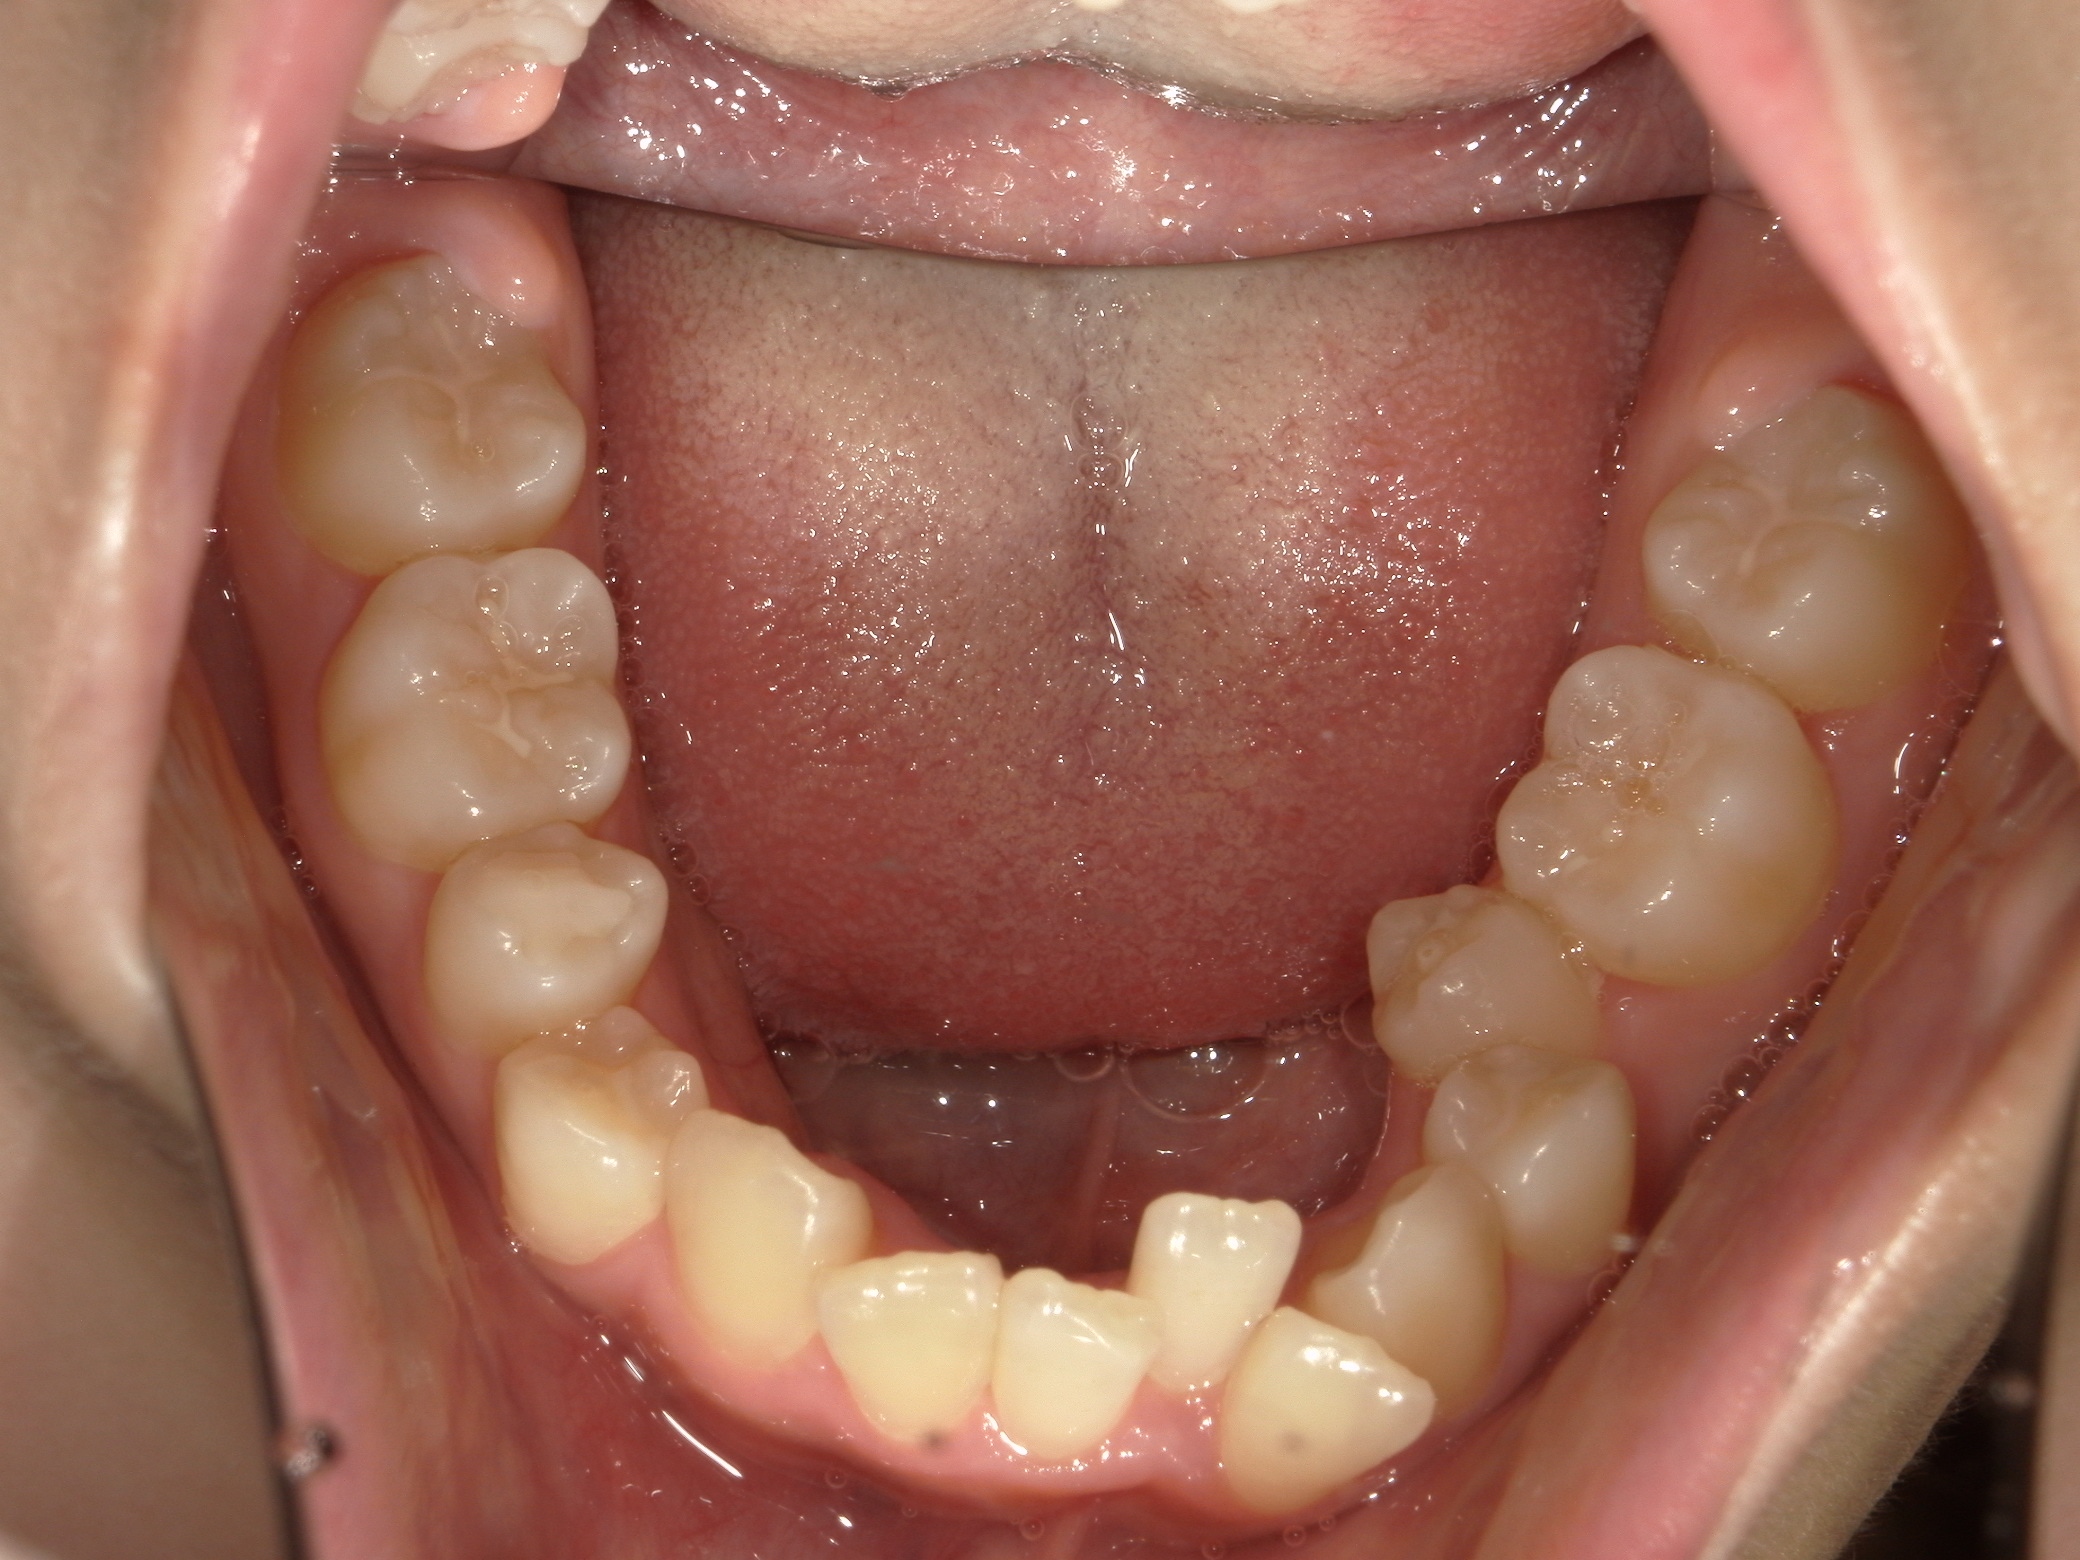

口内下

治療前

上下の歯並びに凹凸があり、前歯の咬み合わせが深い状態でした。

歯を並べる隙間を作るため、上下共に歯を抜いて治療を行うこととしました。

上は矮小歯を、下は横の歯を抜いて治療を行いました。